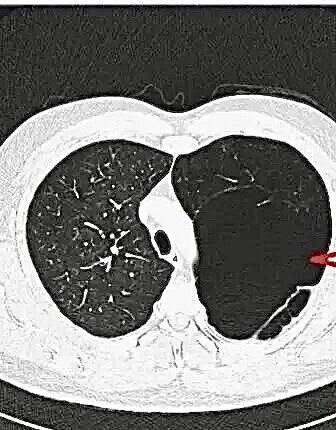

最近常常有患者拿著胸部CT來(lái)咨詢關(guān)于肺大泡的一些問(wèn)題,很多人在網(wǎng)上查閱資料后發(fā)現(xiàn)肺大泡無(wú)法用藥根治,頓時(shí)茶飯不思,在這里我們帶大家正確認(rèn)識(shí)肺大泡。什么是肺大泡?肺大泡,是指由于各種原因?qū)е路闻萸粌?nèi)壓力升高,肺泡壁破裂,互相融合,在肺組織形成的含氣囊腔。肺大泡定義為擴(kuò)張狀態(tài)下,直徑超過(guò)1cm的肺內(nèi)氣腔(圖1),巨型肺大泡是指至少占據(jù)一側(cè)胸腔30%的大泡(圖2)肺大泡的常見(jiàn)原因是什么?1.氣管的炎性病變?nèi)绶窝住⒎谓Y(jié)核、慢性支氣管炎等,因炎性病變,氣管出現(xiàn)水腫、狹窄,造成管腔部分阻塞,產(chǎn)生活塞作用,空氣能進(jìn)入肺泡而不易排出去,使之肺內(nèi)壓增高。2.吸煙、空氣污染對(duì)于長(zhǎng)期吸煙及其他有害氣體和職業(yè)粉塵吸入史的患者,人體在吸入這些有害的氣體、細(xì)顆粒物后,這些物質(zhì)經(jīng)過(guò)氣管、細(xì)支氣管,最終在肺泡停留沉積下來(lái),它們會(huì)長(zhǎng)時(shí)間的刺激、破壞正常的肺泡結(jié)構(gòu),肺泡壁破裂,從而形成肺氣腫,隨著破壞的進(jìn)一步持續(xù),這些肺氣腫也將進(jìn)一步破壞,融合成片,從而最終形成肺大泡。3.原發(fā)性肺大泡原發(fā)性肺大泡,可能與肺發(fā)育不良有關(guān),多見(jiàn)于體形瘦高的青少年,其原因可能與青春期發(fā)育過(guò)程中,骨骼生長(zhǎng)過(guò)快,肺相對(duì)生長(zhǎng)緩慢,在胸頂和肺尖部有一個(gè)筋膜過(guò)渡牽拉肺尖部組織,導(dǎo)致該處肺組織的肺泡發(fā)育不良形成肺大泡。肺大皰如何治療呢?肺大泡一種不可逆轉(zhuǎn)的肺部病損,一般不能自愈,且目前尚無(wú)特效藥物治療,手術(shù)是治療肺大泡唯一有效的方法,但不是所有的肺大皰均需手術(shù)質(zhì)量。如一些較小的、局限的、數(shù)量少的肺大泡,多不會(huì)引起臨床癥狀,通常不需要治療。由氣道炎癥、肺氣腫等病變導(dǎo)致的肺大泡,需要積極治療原發(fā)病。肺大泡如果大于胸腔的1/3,就被稱為巨大的肺大泡,可能對(duì)周圍的組織形成較大的壓迫,甚至對(duì)生命產(chǎn)生威脅,這種情況要盡快進(jìn)行手術(shù)治療。肺大皰患者的注意事項(xiàng)1.吸煙及空氣污染是肺氣腫的首要誘因,因此遠(yuǎn)離煙草及空氣污染能夠減緩進(jìn)程;2.平時(shí)不要做劇烈的運(yùn)動(dòng),不要手提重物,不要突發(fā)性的大聲咳嗽及大笑,避免肺大泡破裂,產(chǎn)生自發(fā)性氣胸;3.適當(dāng)鍛煉身體,增強(qiáng)身體的抵抗力和免疫力,根據(jù)自身情況,參加一些適當(dāng)?shù)捏w育活動(dòng),注意營(yíng)養(yǎng),多進(jìn)食優(yōu)質(zhì)蛋白質(zhì)以及含維生素較高的食物,提高機(jī)體抵抗力;4.避免呼吸道感染,每次呼吸道感染后肺功能都受影響。對(duì)于慢性阻塞性肺疾病、支氣管哮喘等原發(fā)性疾病,積極治療原發(fā)病,改善肺功能;5.若出現(xiàn)由肺大泡破裂導(dǎo)致的胸痛、胸悶、呼吸困難等不適癥狀,應(yīng)及時(shí)到醫(yī)院治療。?